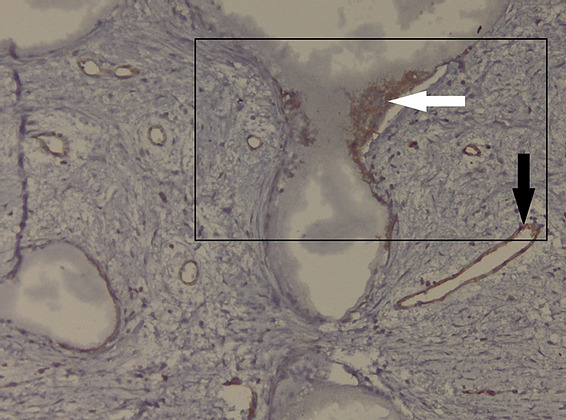

The histolopathological analysis performed shows in the meshes of the prosthetic material, fibrovascular tissue and minimal polymorphic inflammatory infiltrate (lymphocytes, plasma cells and polymorphonuclear neutrophils) and moderately frequent multinucleated giant cells of the “foreign body” type at the interface with the hydroxyapatite as well as osteoclasts at the interface with the hydroxyapatite nanocomposite material. At different levels in the muscle tissue and in the corresponding sclera, amorphous, acellular material (mono and multifilament surgical threads) bordered by multinucleated giant cells of the “foreign body” type is observed. (Figure 11,12). It can be observed that the invasion of the implant with fibrovascular material begins from the incision and the initial suture area, and the presence of multinucleated giant cells of the foreign body type in not very large numbers attests to good compatibility, at least equal to that of the suture material.

Figure 13: Microscopic appearance of the implant – CD31 immunohistochemical staining. The presence of CD31 + osteoclasts at the level of the implant meshes (black frame) of hydroxyapatite (white arrow) and the presence of CD31 + vascular endothelium (black arrow) is noted;